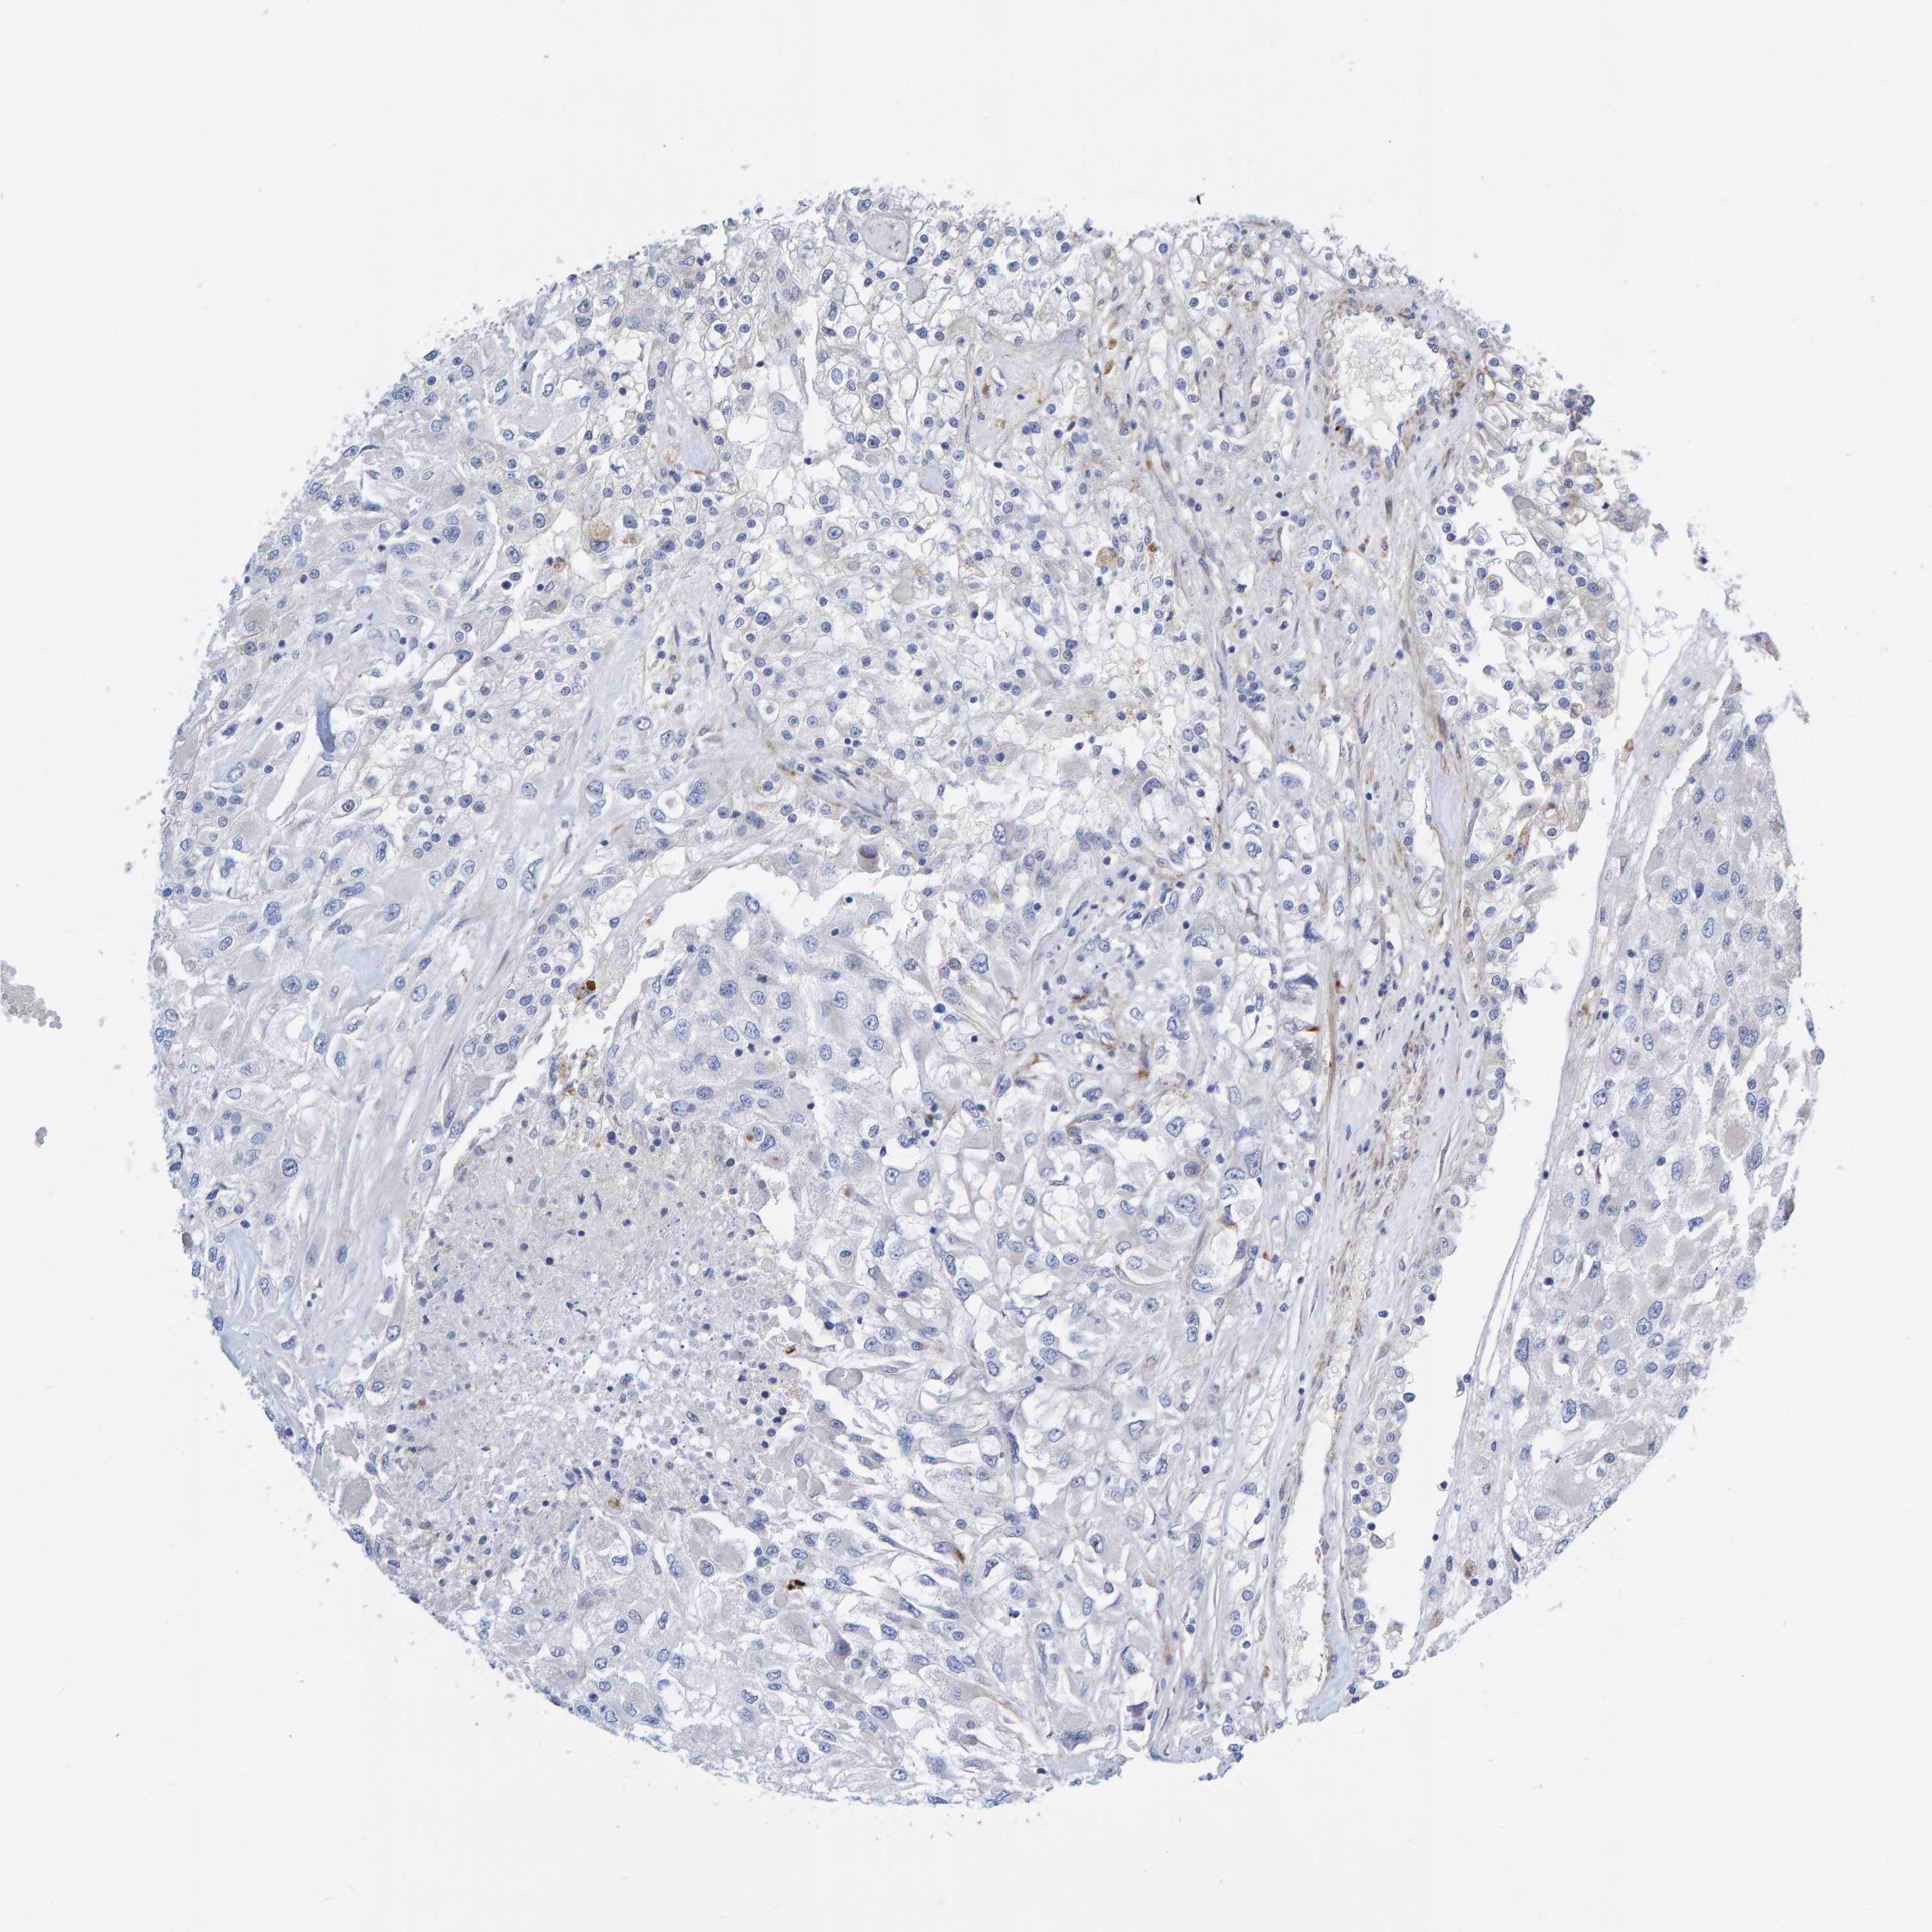

KIDNEY RENAL PAPILLARY CELL CARCINOMA (TCGA) - Interactive survival scatter ploti

The Survival Scatter plot shows the clinical status (i.e. dead or alive) for all individuals in the patient cohort, based on the same data that underlies the corresponding Kaplan-Meier plots. Patients that are alive at last time for follow-up are shown in blue and patients who have died during the study are shown in red.

The x-axis shows the expression levels (FPKM) of the investigated gene in the tumor tissue at the time of diagnosis. The y-axis shows the follow-up time after diagnosis (years). Both axes are complimented with kernel density curves demonstrating the data density over the axes. The top density plot shows the expression levels (FPKM) distribution among dead (red) and alive patients (blue). The right density plot shows the data density of the survived years of dead patients with high and low expression levels respectively, stratified using the cutoff indicated by the vertical dashed line through the Survival Scatter plot. This cutoff is automatically defined based on the FPKM cutoff that minimizes the p-score. The cutoff can be changed by dragging the vertical line or by entering a cutoff value in the square labeled "Current cut-off".

Under the Survival Scatter plot the p-score landscape (black curve; left axis) is shown together with dead median separation (red curve; right axis). Dead median separation is the difference in median mRNA expression between patients who have died with high and low expression, respectively. It is calculated as follows: median FPKM expression of dead patients with high expression - median FPKM expression of dead patients with low expression. This is intended to aid the user in visually exploring custom cutoffs and the associated p-scores and dead median separation.

Individual patient data is displayed and can be filtered by clicking on one or more of the category buttons on the top of the page. Categories describing expression level and patient information include: high, low, alive, dead, female, male and tumor stages. The scale of the x-axis can be toggled between linear and log-scale by clicking on the "x log" button. Mouse-over function shows TCGA ID, patient information and mRNA expression (FPKM) for each patient.

& Survival analysisi

Kaplan-Meier plots summarize results from analysis of correlation between mRNA expression level and patient survival. Patients were divided based on level of expression into one of the two groups "low" (under cut off) or "high" (over cut off). X-axis shows time for survival (years) and y-axis shows the probability of survival, where 1.0 corresponds to 100 percent.

POLG2 is not prognostic in Kidney Renal Papillary Cell Carcinoma (TCGA)

Best expression cut offi

Based on the FPKM value of each gene, patients were classified into two groups and association between prognosis (survival) and gene expression (FPKM) was examined. The best expression cut-off refers the FPKM value that yields maximal difference with regard to survival between the two groups at the lowest log-rank P-value. Best expression cut-off was selected based on survival analysis .

When clicking on this number, the vertical dashed line indicating cut-off, the interactive survival plot, and the Kaplan-Meier curve will be adjusted to show results based on the best expression cut-off.

: 4.34